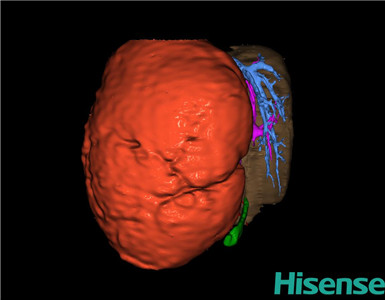

术前三维重建及手术方案设计:

将0.625mm双源薄层CT资料的静脉期和动脉期Dicom格式文件导入海信CAS系统。

通过调节窗宽窗位调整CT序号,对肝实质,胆囊,下腔静脉,肿瘤,肝动脉、门静脉及肝静脉等进行三维重建;系统自动计算肝脏体积。

模拟手术操作,自动计算切除肝体积、肿瘤体积、剩余功能性肝体积。

肝脏体积为218.1ml,肿瘤体积为1570ml,肿瘤体积为肝脏体积的7.2倍,通过比对1-3月正常肝脏体积为174.85±58.11ml,通过术前模拟手术,精准判断切除后剩余肝脏体积能耐受,避免肝衰竭发生。

术前三维重建:

重建图片